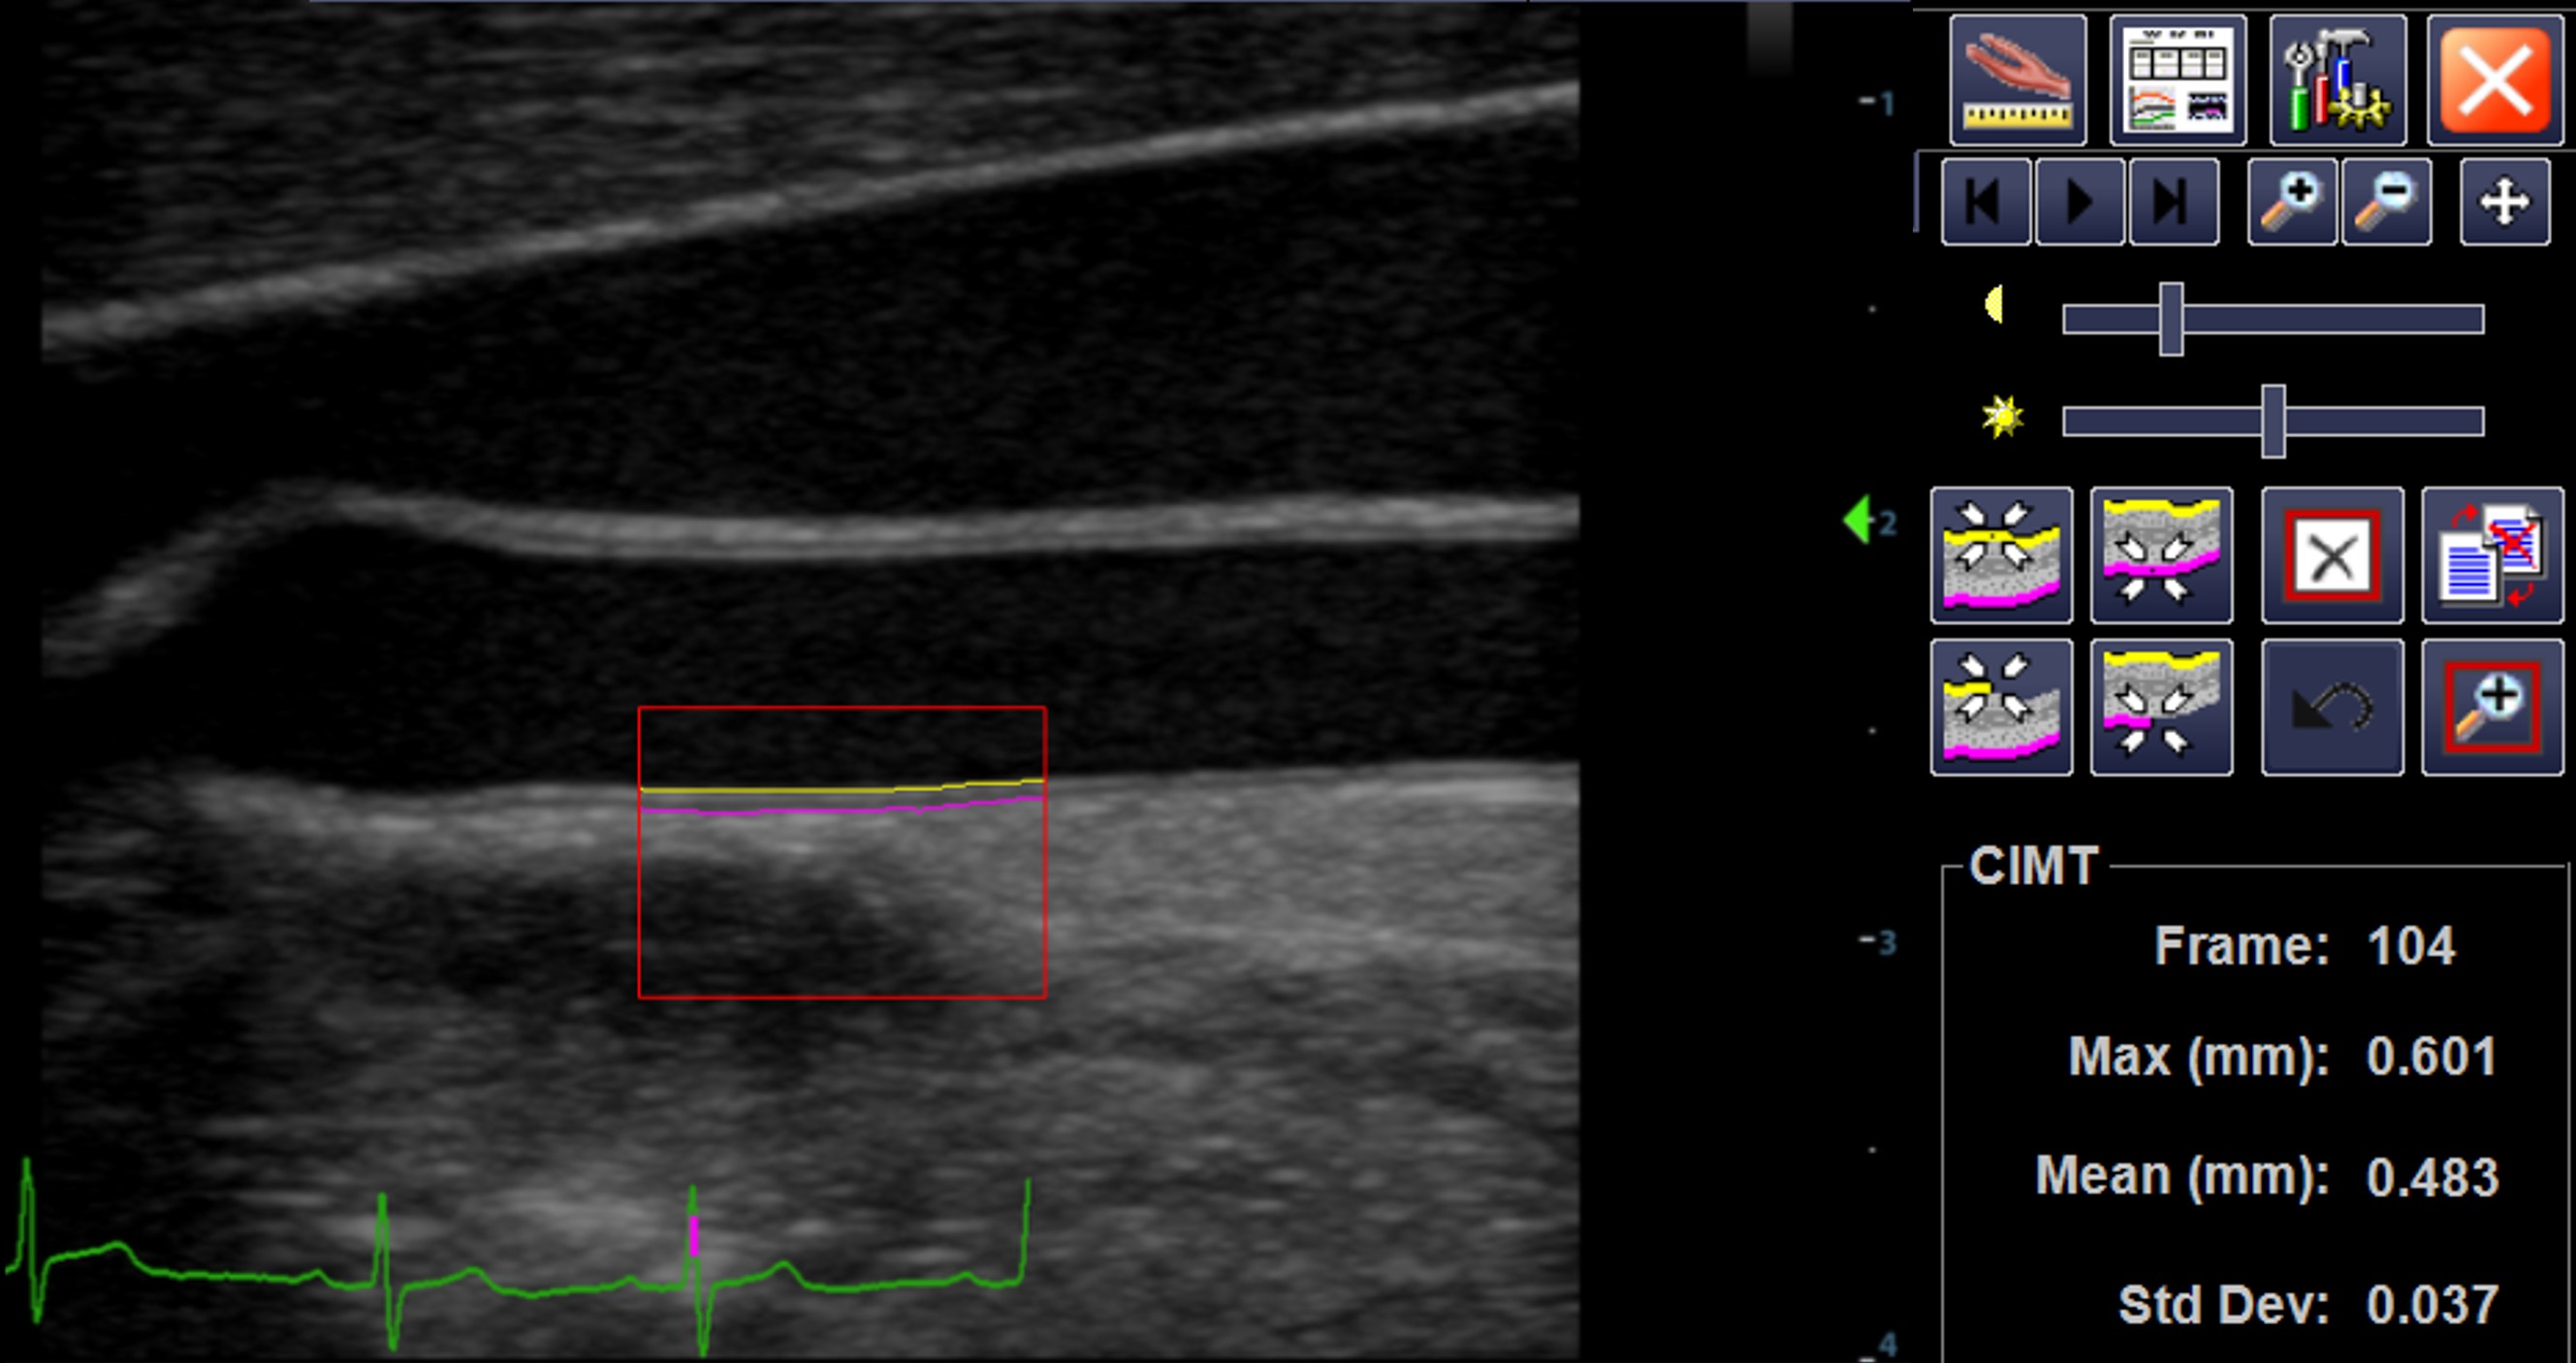

Below demonstrates measurement of far wall common carotid artery intima-media thickness.